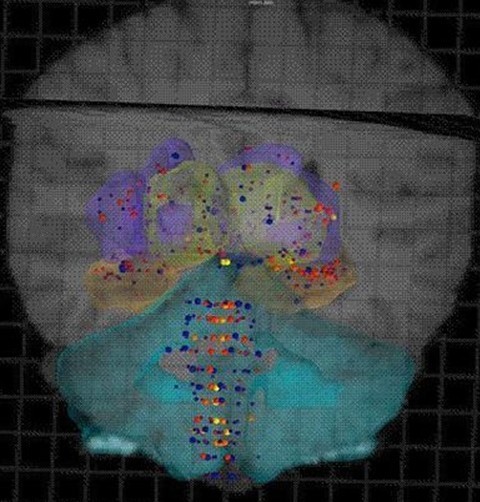

科學家將相關數據編制成一個名為“艾倫人腦圖譜”的數據庫,該圖譜除了顯著標識出人類基因圖譜中的每個基因在大腦的何處表達之外,還涵蓋了大腦核磁共振成像(MRI)和磁共振彌散張量成像(DTI)提供的數據,供公眾自由免費訪問。這些數據顯示,人腦之間的相似度高達94%,至少82%的人類基因都會在大腦中表達。

與高性能、多功能的全球定位系統(GPS)一樣,艾倫人腦圖譜確定了人腦中的1000個解剖點,指明了每個點上特定的基因表達和基本的生物化學特性?茖W家能借用艾倫人腦圖譜探測人腦,厘清人腦遭受的疾病和損傷(包括生理損傷和精神健康疾。⿲Υ竽X特定區域的影響。科學家有望借此準確定位出某種特定的藥物應作用于大腦的哪個區域并最終更好地控制很多療法的治療結果。